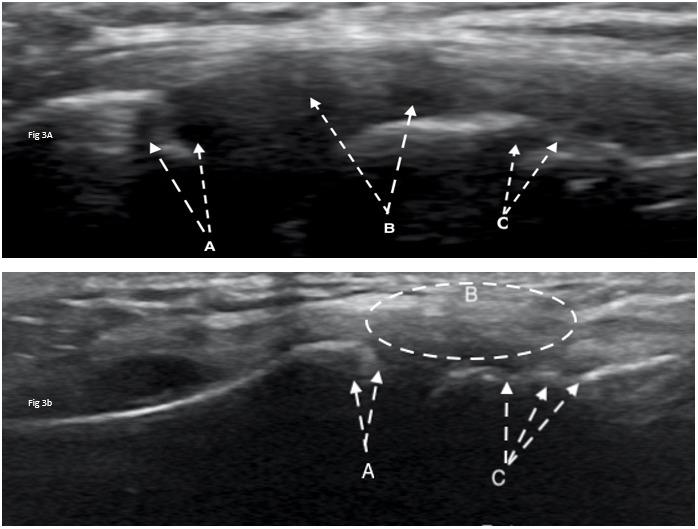

The Use of MSK Ultrasound with Quadriceps Muscle Injury.

Manske R, Voight M, Wolfe C, Page P.